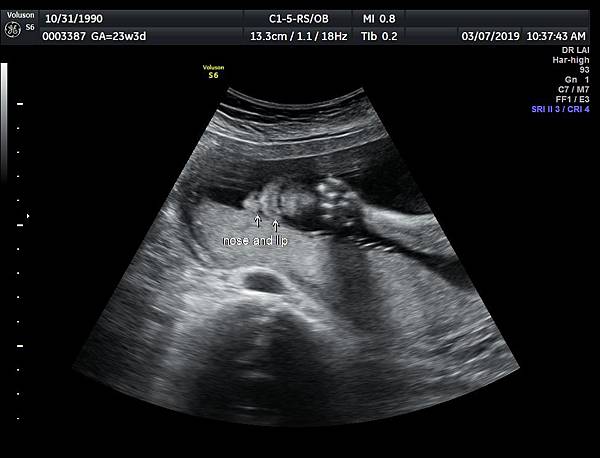

2017年8月12日一位22歲第二胎的孕婦在診所接受胎兒高層次及心臟超音波檢查,她說因為第一胎沒有兔唇但是顎裂,上網搜尋相關資訊所以來到診所安排檢查:她知道我會看懸雍垂(因為懸雍垂是軟顎最後形成的位置,如果看到完整懸雍垂,可以間接診斷正常的顎)

一個檢查如果要花很長的時間才能完成,這樣的檢查無法變成常規的篩檢方式,我已經在我的診所執行懸雍垂檢查一段時間,我檢查懸雍垂大約30 秒,前提是胎兒的臉最佳位置是側躺,其次是側躺偏向上,我的檢查步驟是上顎(含日後大門牙長出的位置)、舌頭、懸雍垂(= equal sign)(附圖1~8),如果超過60秒無法完成,只有兩個原因,一個是胎兒姿勢不適合或喉嚨羊水空間太小,這時候不要硬碰硬,只要先檢查其他部位,等待時機再回來即可,我的經驗是90%的cases都能順利完成這項檢查(肚皮厚的case真的是很難)。